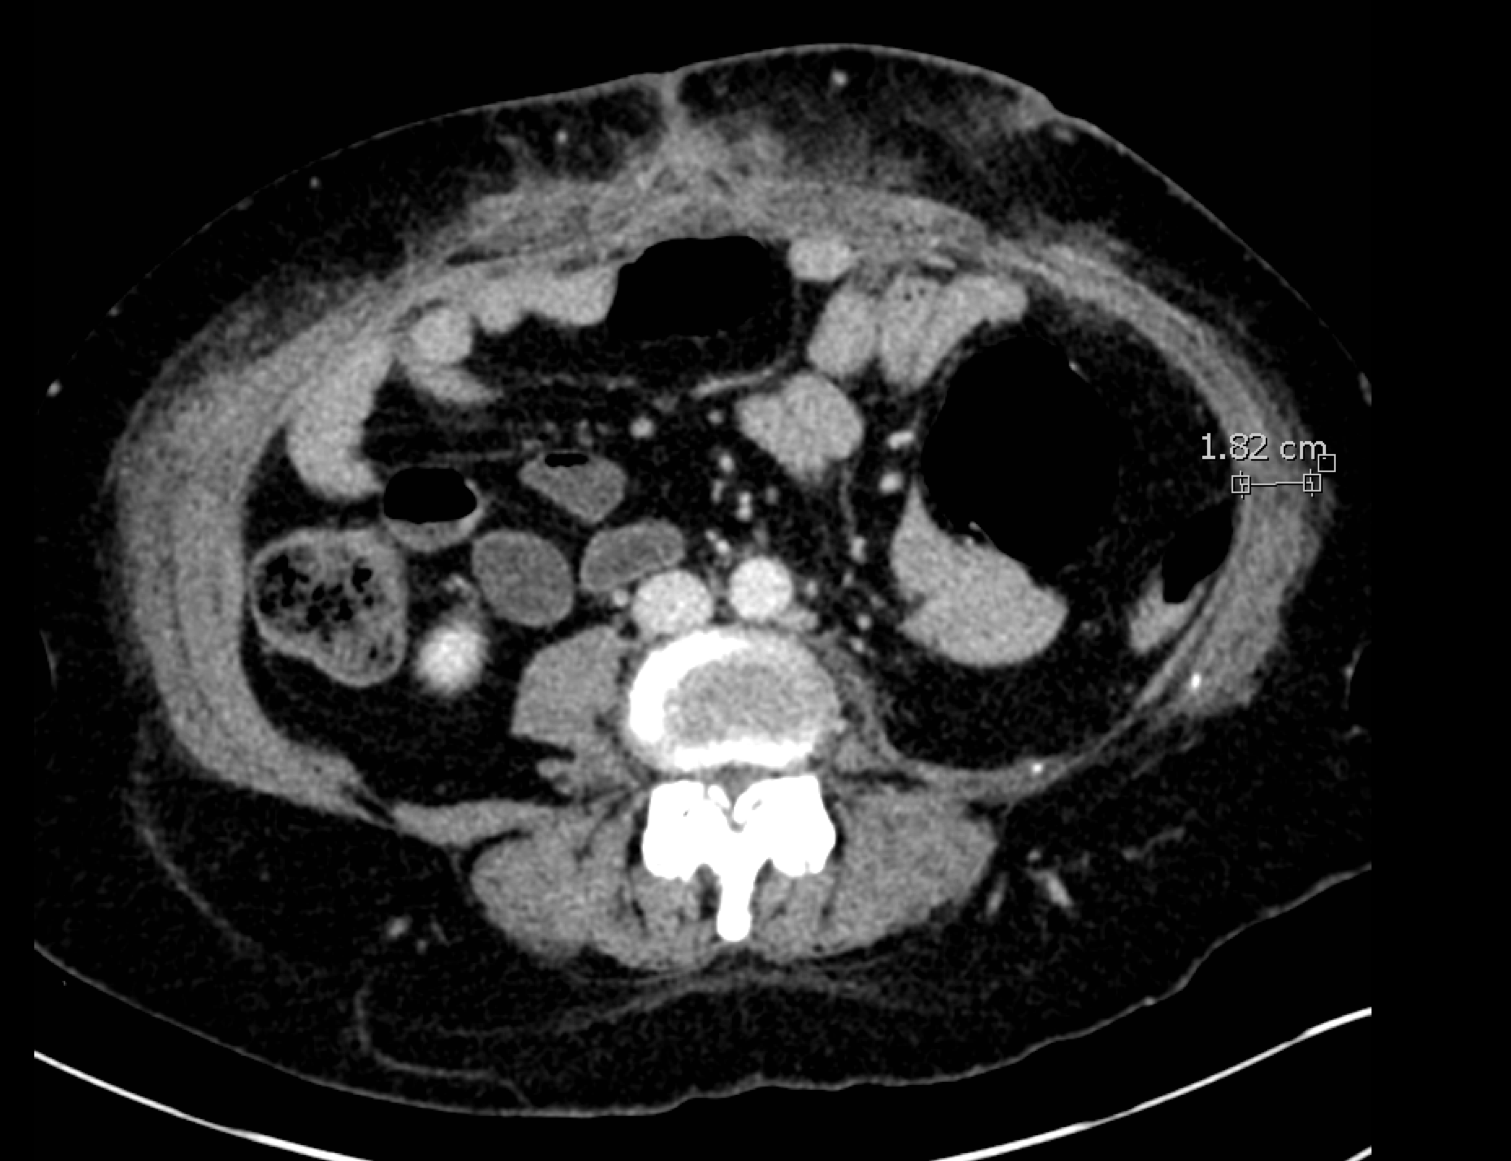

These CT scans of a cross-section of Goff's abdomen show how the Botox enabled Eriksson to pull her abdominal muscles back into position. At top, pre-surgery, the hernia is visible at the top of the scan. A measurement shows the right abdominal muscle has retracted and, as a consequence, has thickened to a width 2.85 cm. In the lower image, the muscle has been stretched thinner, so the new measured width is 1.82 cm, and pulled back to the center of her body. Images provided